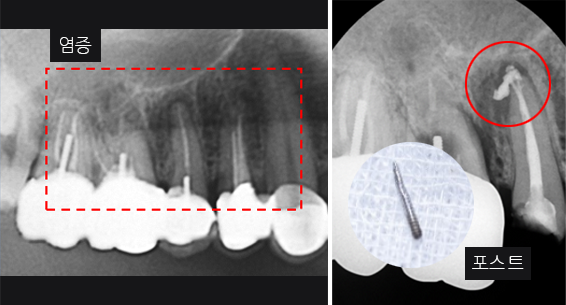

치근단 염증

캐스팅 포스트 제작

캐스팅 포스트

크라운치료

크라운을 하기 전에 신경 치료를 위해 뚫어 놓은 구멍을 단단한 재료로 메우는 것이 필요합니다. 보통 코어, 핀 포스트, 캐스팅포스트, 파이버 포스트와 같은 종류가 있으며 외부에서 힘을 가해져도 치아가 부러지지 않고 남은 치아의 구조물에 잘 붙어 있도록 합니다. 충치가 많이 진행되어 치아 부분이 많이 없거나 치아가 약한 경우에 필요합니다.